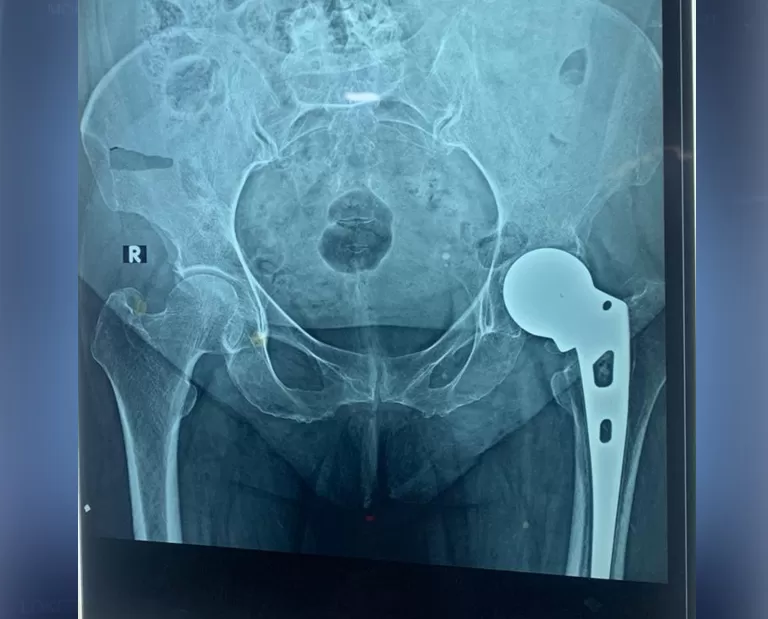

Mrs. Vimla Ji

Name: Mrs. Vimla Ji

Date of Operation: 18 Aug 2022

Age: 54 Years

THR (Total Hip Replacement)